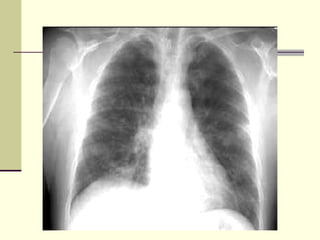

NORMAL CHEST X-RAY L- Lung T- Trachea AK- Aortic Knob A- Ascending Aorta H- Heart R- Ribs P- Pulmonary Artery S- Spleen

NORMAL CHEST X-RAYL- Lung T- Trachea AK- Aortic Knob A- Ascending Aorta H- Heart R- Ribs P- Pulmonary Artery S- Spleen